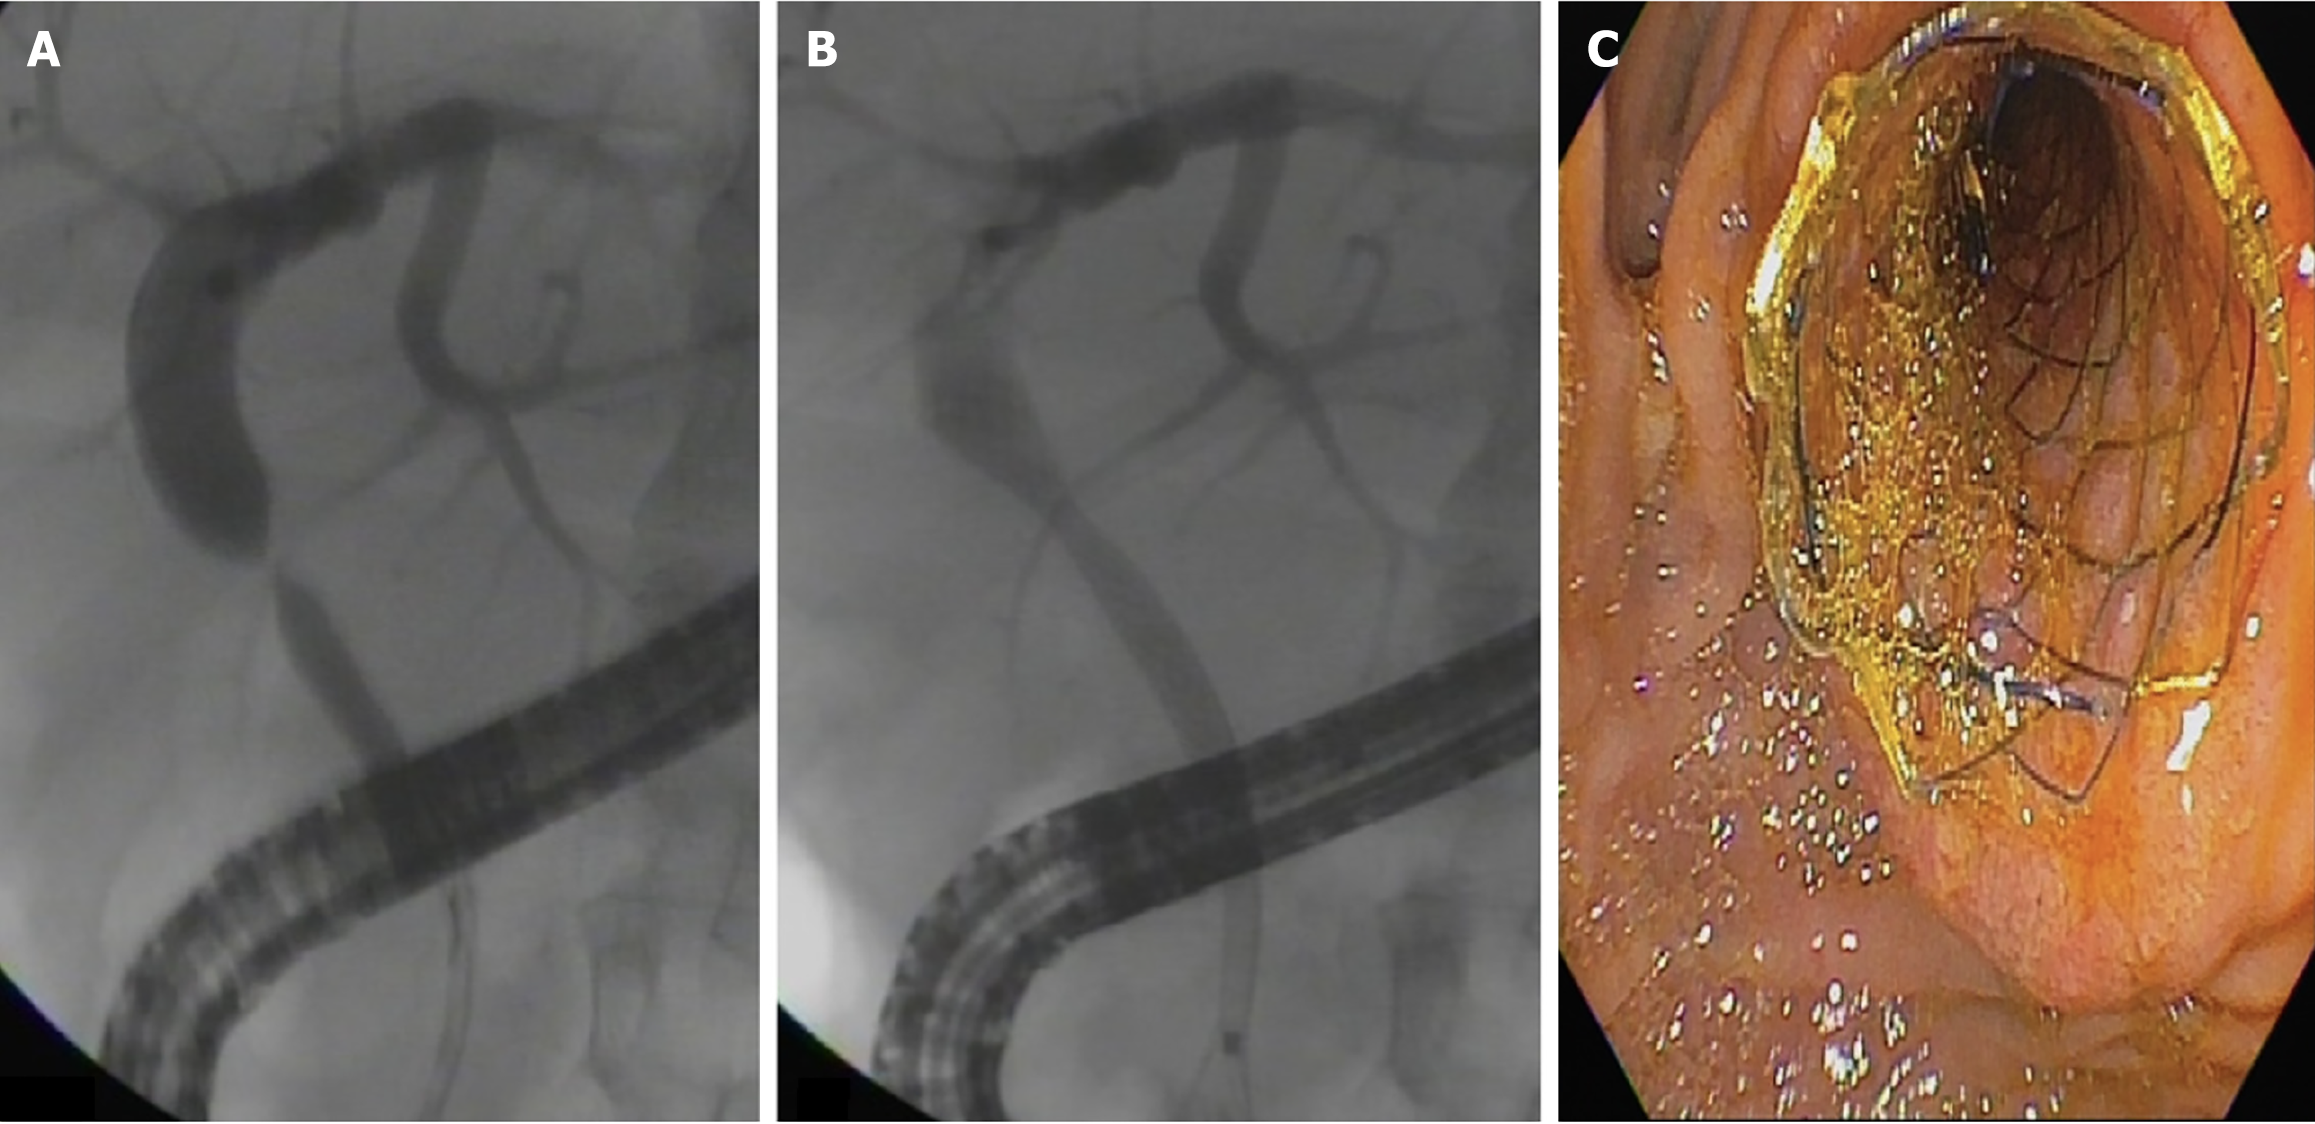

At the beginning of the study period, patients treated with cSEMSs had their stent removed after 6 months. Later in the study, with new evidence from the literature, the cSEMS were removed after 12 months. Patients were monitored for clinical signs of cholestasis. ERCP was performed whenever necessary at any time during follow-up. Patients without complications were followed for at least 12 months to remove the stent and evaluate stricture resolution. Patients who developed BASs within 30 days of liver transplantation were initially treated with MPS placement. If the stricture persisted following stent removal, the patients were re-evaluated for further treatment with MPSs. The treatment strategies using MPSs and cSEMSs are shown in Figures 1 and 2, respectively.

Stricture resolution: Overall stricture resolution occurred in 101/104 patients (97.1%): (1) 83/84 (99%) in the cSEMS group; and (2) 18/20 (90%) in the MPS group (P = 0.094). There was no difference between the cSEMS and MPS groups after an average 3-year follow-up. Endoscopic failure occurred in 3 patients: (1) Two in the MPS group; and (2) One in the cSEMS group. All were referred for surgery (Roux-en-Y bilioenteric anastomosis) (Figure 4).